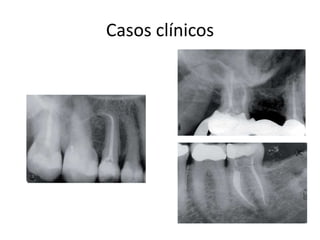

Casos clínicos